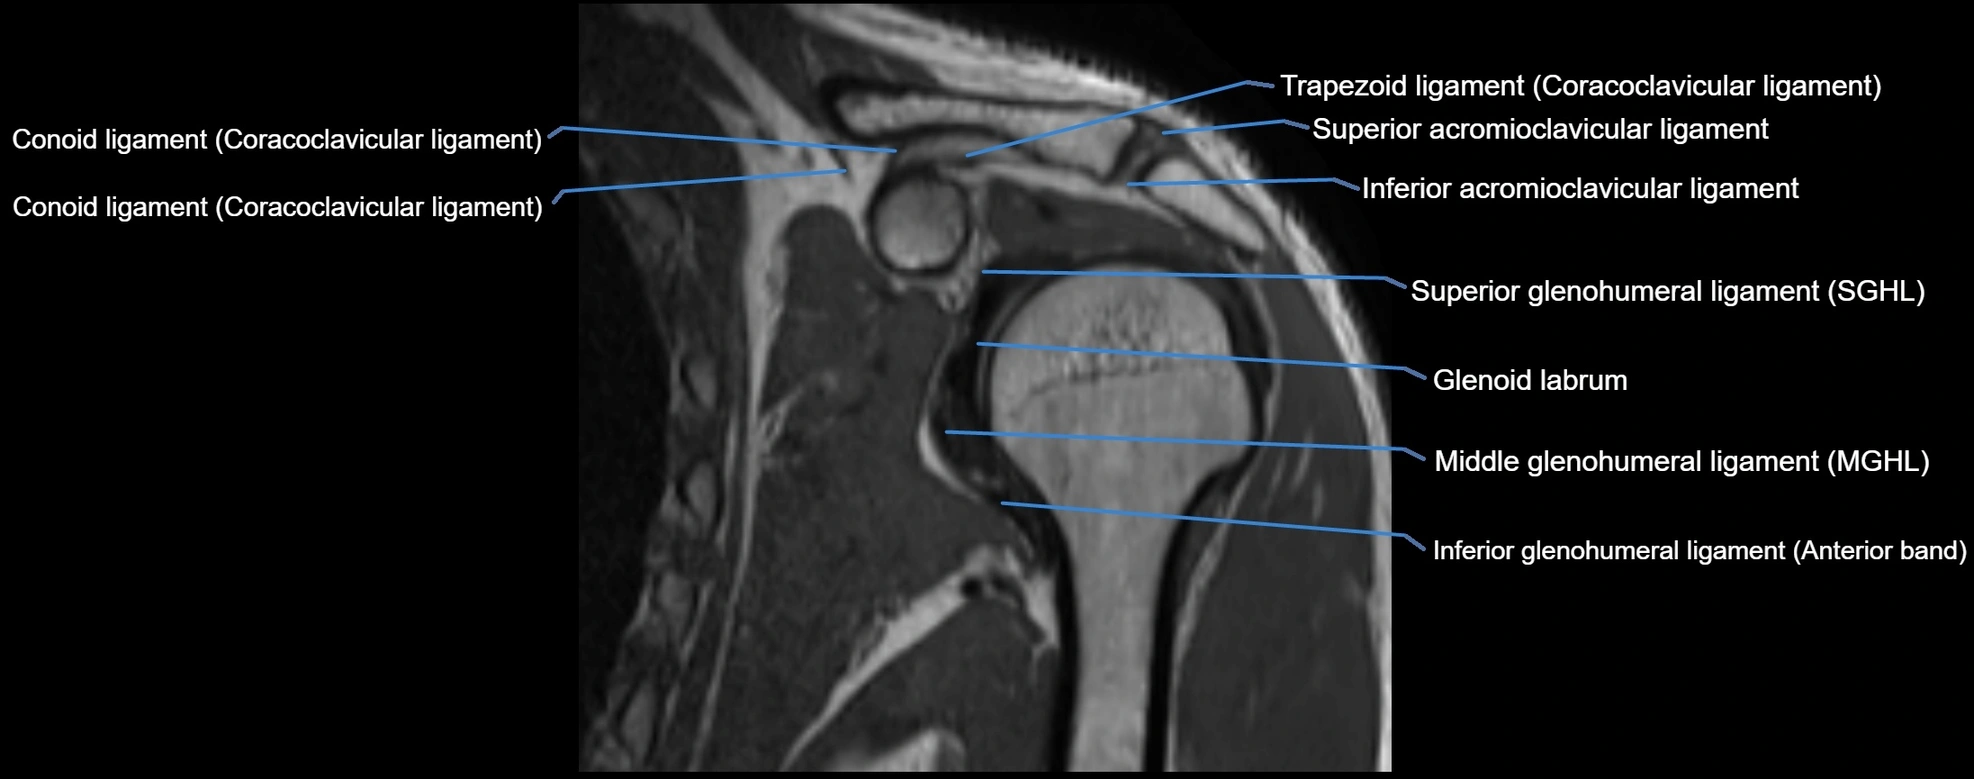

MRI Appearance

• T1-weighted images:

• Normal ligament: Low signal (dark linear band) spanning acromion to clavicle.

• Surrounding fat planes: Bright, delineating the ligament clearly.

• Marrow of clavicle and acromion: Bright due to fatty content.

• Tears: Discontinuity or irregular thickening with intermediate-to-bright signal.

• Chronic injury: Thinning, fraying, or irregular low-signal fibers with adjacent scarring.

• T2-weighted images:

• Normal ligament: Low signal, homogeneous.

• Partial tear or sprain: Focal hyperintensity or thickening.

• Complete tear: Discontinuity with fluid-bright gap between clavicle and acromion.

• Associated edema: Bright signal in distal clavicle or acromion marrow.

• Proton Density Fat-Saturated (PD FS):

• Normal ligament: Low signal, uniform thickness.

• Partial tear or sprain: Bright signal or contour irregularity.

• Complete tear: Clear discontinuity with bright signal gap and joint effusion.

• Excellent for assessing joint capsule, coracoclavicular ligaments, and periarticular edema.

MRI images

image